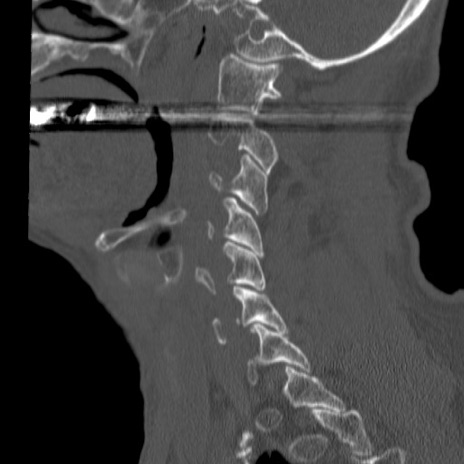

症例46 頚椎CT(矢状断像)

【症例】80歳代男性

【主訴】両側頚部〜上肢のしびれ

【現病歴】昨日、自宅内で転倒、その後より上記症状あり。意識障害なし。

【身体所見】両側上肢のallodynia(熱痛覚過敏)あり。MMTおよびDTRは正確な所見取れず。両上肢の挙上はなんとか可能。

異常所見と診断は?